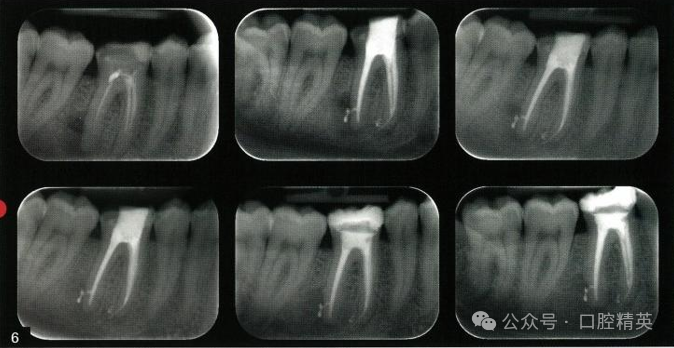

6、什么时间能确定牙髓源性根尖周病变正在愈合?

图:6 牙髓源性根尖周病变的 愈合时间存在显著差异,因此 必须长期随访。